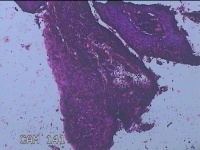

宫颈6点、12点组织

性别

女

年龄

57岁

临床诊断

子宫颈上皮内瘤变[CINⅢ级];子宫颈肿瘤

一般病史

阴道不规则出血1年。

标本名称

大体所见

1.“宫颈6点组织”:灰白粉红色组织1.3x0.8x0.3cm一块。 2.“宫颈12点组织”:灰白粉红色组织1.5x0.7x0.2cm一块。

图2